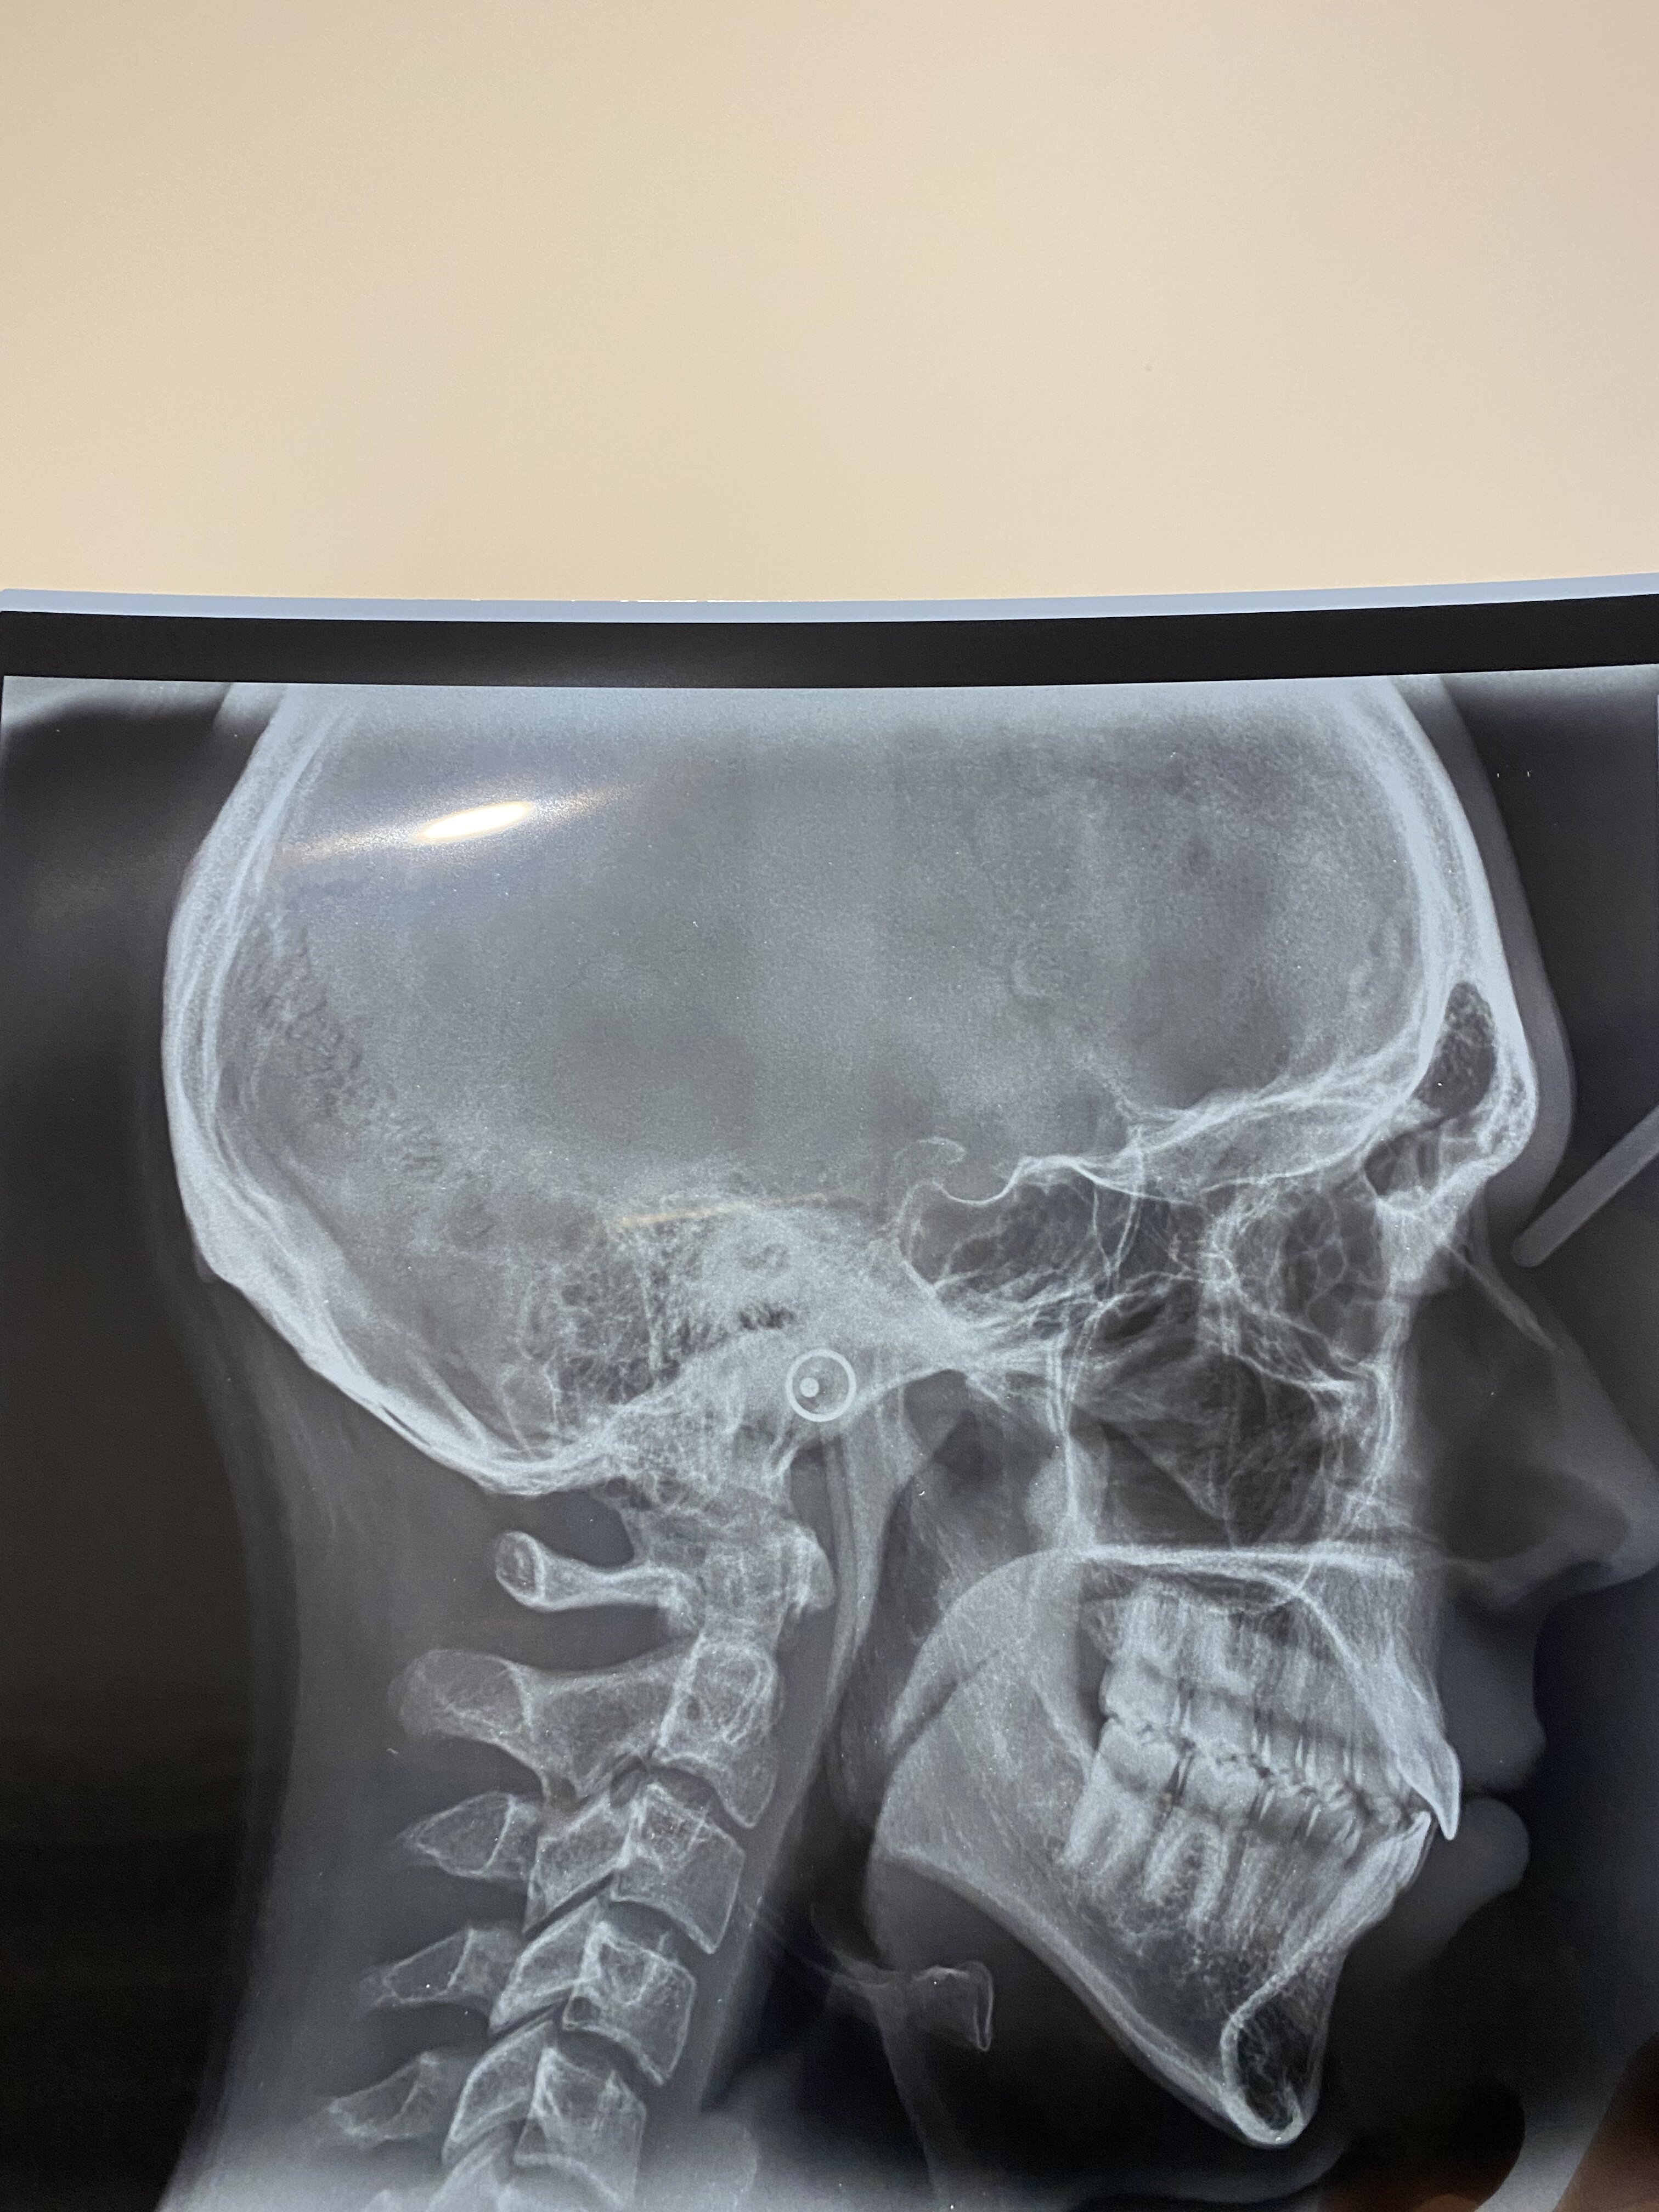

DJS + Genioplasty pre-planning

Mandible and maxilla, osteo ues or osteectomies of, involving 2 such procedures of each jaw; including transposition of nerves and vessels and bone grafts taken from the same site and stabilisation with fixation by wires, screws, plates or pins or any combination.